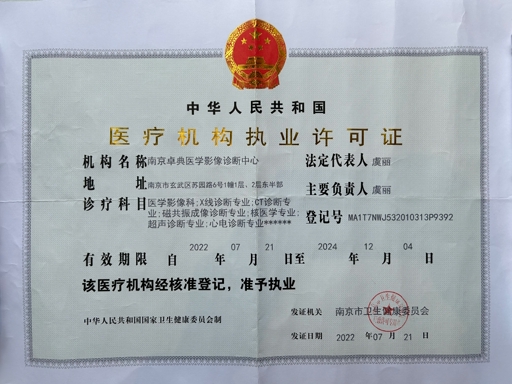

医疗资质认证

江苏省首家第三方独立医学影像诊断中心,具备完整的资质认证,确保服务的合法性和专业性

权威认证保障

所有证书均由相关政府部门和权威机构颁发,确保我们的服务符合国家法规要求,为合作伙伴提供可靠的质量保障。我们承诺持续更新和维护各项资质认证,确保服务的合规性和专业性。

合规资质

持有正规《医疗机构执业许可证》,所有医师均具备中级职称以上资质,合作医疗机构无需承担合规风险